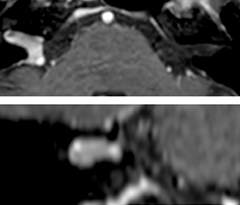

So, what is the actual impact of having more information and more diagnostic confidence? According to Dr. Savatovsky, “One of the indications I’ve seen where using Elition is most impactful is in patients with suspected giant cell arteritis. As an ophthalmologic hospital, we see many patients with suspected giant cell arteritis. Usually we were performing MRI to help us rule out an ischemic stroke, and to verify that the supra aortic vessels are undamaged. With Elition, we still do this, but now we can add on more detailed high-resolution black-blood sequences on superficial arteries. This provides us with high confidence levels for diagnosis of giant cell arteritis (GCA) and as a result, some patients are not sent for a biopsy anymore. A patient who has a normal MRI will not require a biopsy and can be discharged from the hospital in the same day. Before, such a patient would have to stay for about a week, just to find that their biopsy results were negative. We have at least three or four patients a week with suspected giant cell arteritis. For a great deal of these patients we can have a direct impact on their hospital stay.”

The 3D TSE T1w black blood MSDE sequence with fat suppression has an isotropic 0.8 mm voxel size and sagittal oblique and axial reformats are made. The images show superficial temporal artery thickening and peri-arterial fat infiltration. The 3D TSE PDw black blood MSDE with fat suppression has 0.55 mm isotropic voxels. The images shows focal involvement of the frontal branch of the superficial temporal artery.